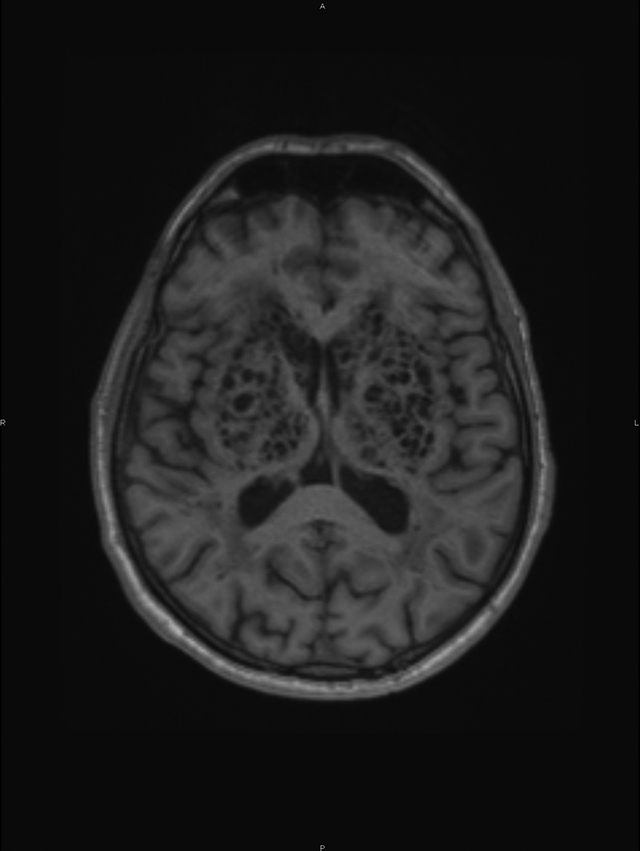

A conglomerate of multiple, symmetric, well-circumscribed round/oval lesions. These lesions presented high signal in T2-weighted sequence (Figure 1) and low signal in T1 (Figure 2) and in T2 fluid-attenuated inversion recovery (Figure 3). No diffusion abnormalities were identified. No enhancement was detected after contrast media administration.

Figure 1

High signal in T2 weighted sequence.